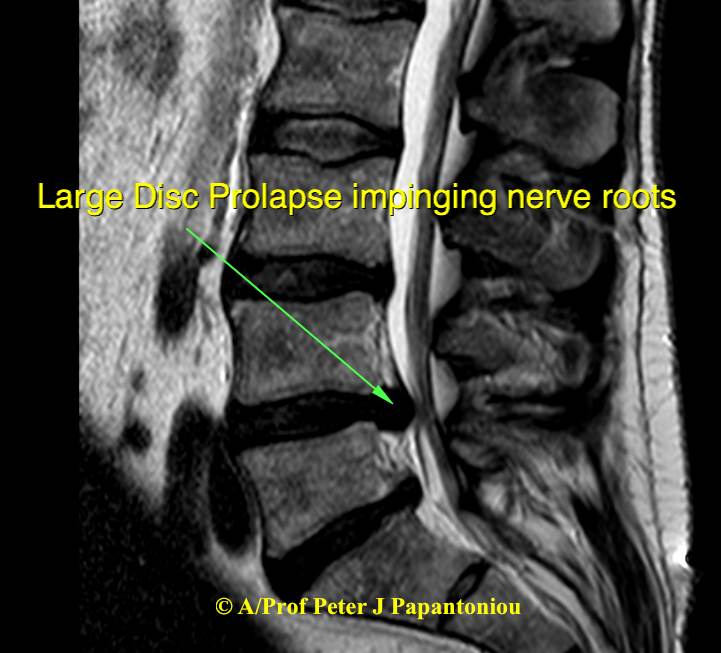

Large Disc Prolapse Large Disc Prolapse sagittal 2

A disc prolapse, also known as a herniated disc or slipped disc, occurs when the soft, spongy material (nucleus pulposus) inside a spinal disc bulges out through a crack in the tougher exterior (annulus fibrosis). This can put pressure on nearby nerves, causing pain and other symptoms such as tingling or numbness in the limbs.